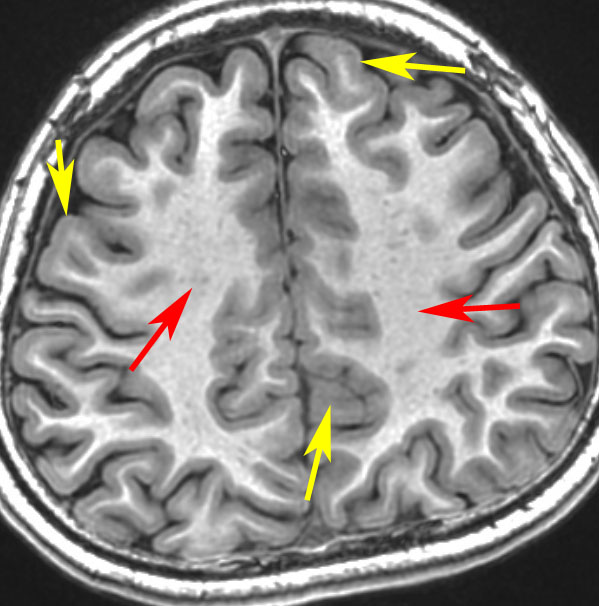

黄色い矢印が灰白質(灰色に見える),赤い矢印が白質です(白く見える)